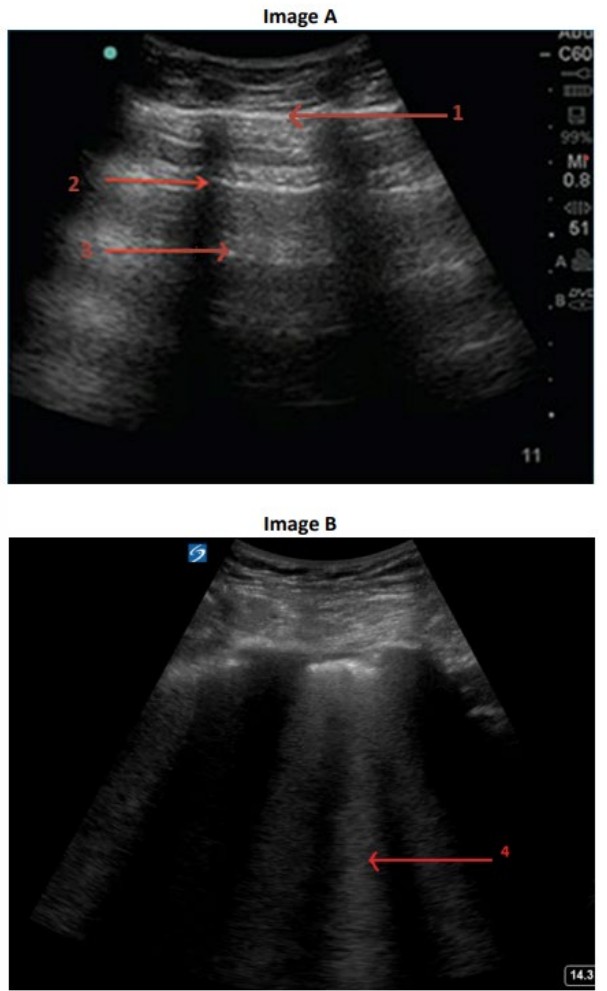

SOB POCUS

You are performing a POCUS lung scan on a 65-year-old man with acute shortness of breath. He has a history …